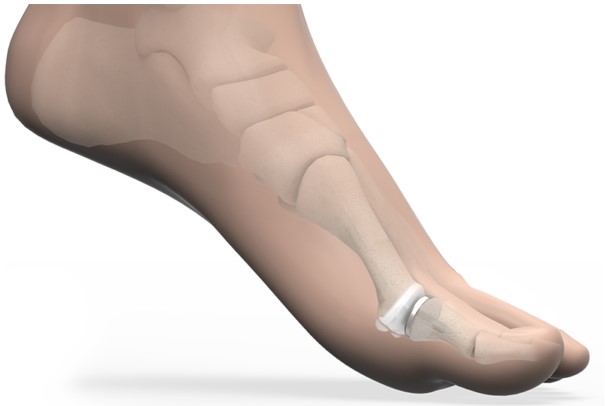

Метою ендопротезування суглоба великого пальця стопи є відновлення рухливості та усунення болю шляхом вставки штучних компонентів, що імітують природний рух суглоба.

Операція з ендопротезування суглоба великого пальця стопи – це складна та незворотна процедура, яка вимагає ретельного обмірковування та планування. Вона включає видалення пошкодженої кістки та хряща, а потім точне встановлення ендопротеза – штучного аналога суглобових поверхонь.

Варіант ендопротезування від BioPro MPJ Hemi замінює суглобовий хрящ з одного боку суглоба (проксимальна фаланга) гладким та міцним імплантатом. Усуваючи контакт кістки з кісткою, імплантат забезпечує знеболення та відновлення рухів. Конструкція запобігає впливу на імплантат високих сил, до 119% ваги тіла, що діють на головку плеснової кістки під час ходьби

Стандартний імплантат виготовлено з кобальт-хрому, біосумісного металу з довгою історією безпечного використання в ендопротезуванні суглобів. Однак, оскільки кобальт-хром містить невелику кількість нікелю, він може не підходити пацієнтам з чутливістю до нікелю. У таких випадках ми пропонуємо титанову альтернативу